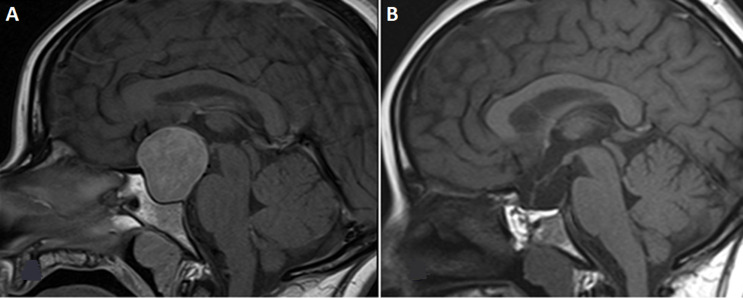

We report the case of a functional gonadotropic adenoma (FGA) in a 32-year-old woman, initially revealed by ovarian hyperstimulation. Hormonal investigations strongly suggested an FGA; pelvic ultrasound revealed macrofollicular ovarian enlargement. Despite a clear clinical picture, diagnosis was delayed until the appearance of cranial tumor syndrome with ophthalmological impairment and pituitary dysfunction. The ophthalmological emergency necessitated urgent surgery, allowing both decompression of the optic pathways and a reduction in hyperestrogenism. Despite their rarity, it is essential to recognize FGA to avoid potentially fatal complications.